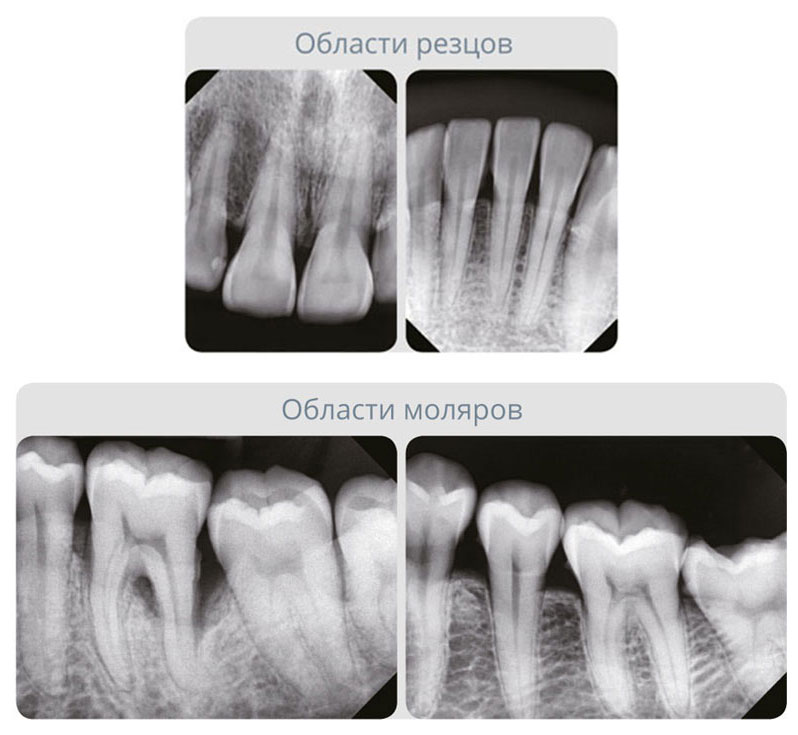

Размер пикселя матрицы 14,8 мкм - наименьший размер среди аналогов

Cтабильно высокое разрешение и более четкие изображения для точной диагностики и планирования лечения.

Долгие годы на рынке традиционных цифровых сенсоров не появлялось по-настоящему инновационных технологий. EzSensor Soft отличается размером пикселя 14,8 мкм! Чем меньше размер пикселя, тем четче диагностические изображения. При 14,8 мкм EzSensor Soft имеет теоретическое разрешение 33,78 пл/мм.